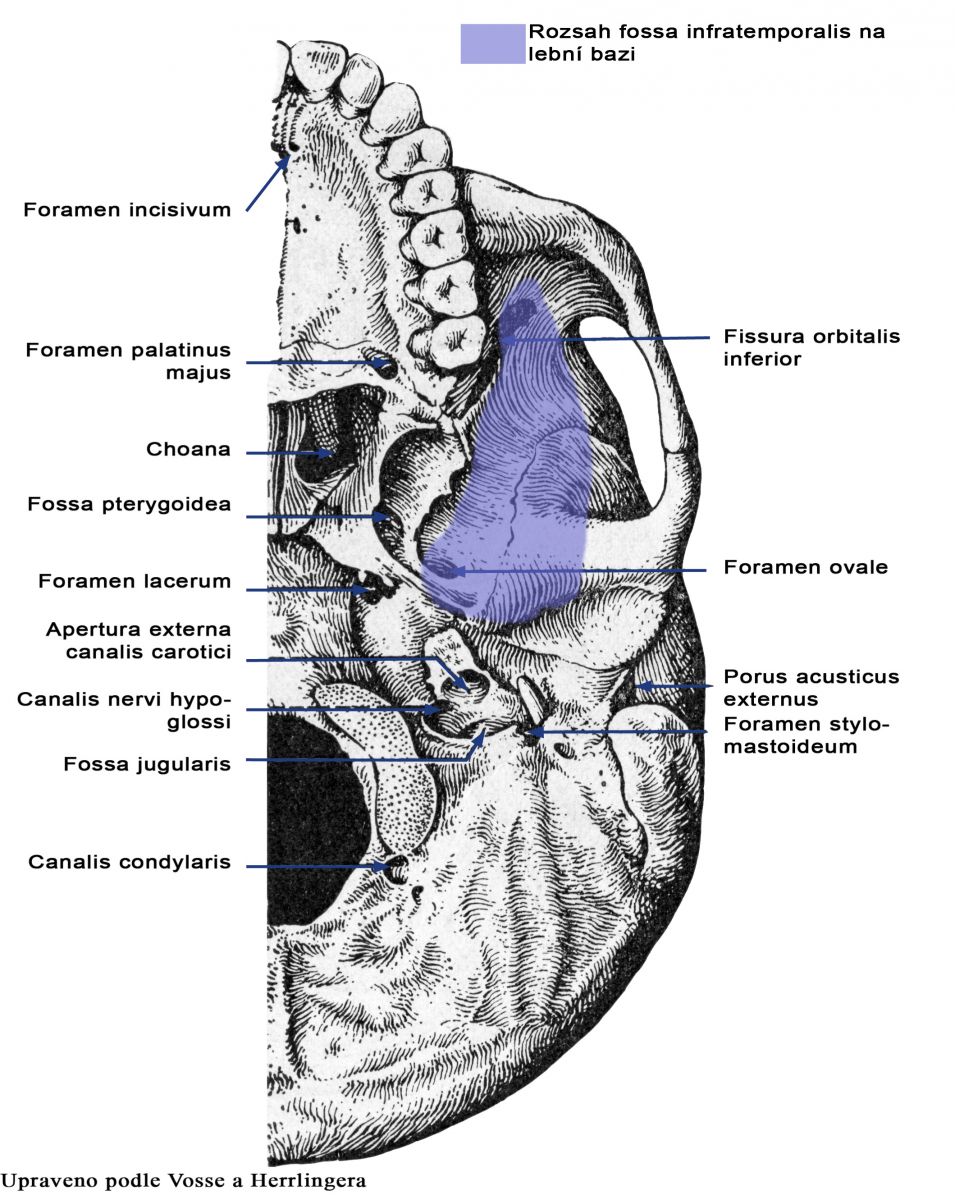

Анатомические особенности: фотографии ямок черепа, височной и подвисочной крылонебной